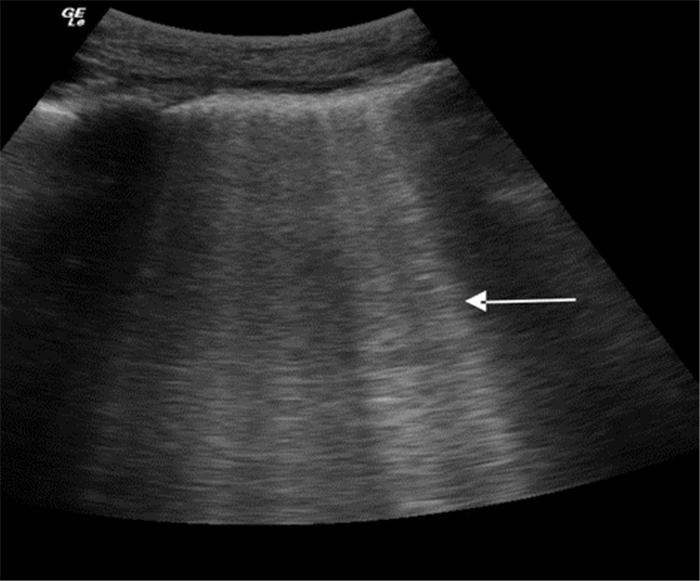

脏、壁层胸膜分离,其间出现无回声区。超声能检测到的最少液体量为20 mL,敏感度高于胸部X线片。

2.2.2 胸膜滑动征消失M型超声下因肺滑动消失而导致“沙滩征”被“条码征”取代(图 10),多见于气胸患者,单纯胸膜滑动征消失还可见于呼吸暂停、肺不张、右主支气管插管或胸膜粘连患者。

| 图 10 条码征及箭头所示的“肺点” |

即“沙滩征”与“条码征”的交点(图 10),提示气胸诊断。